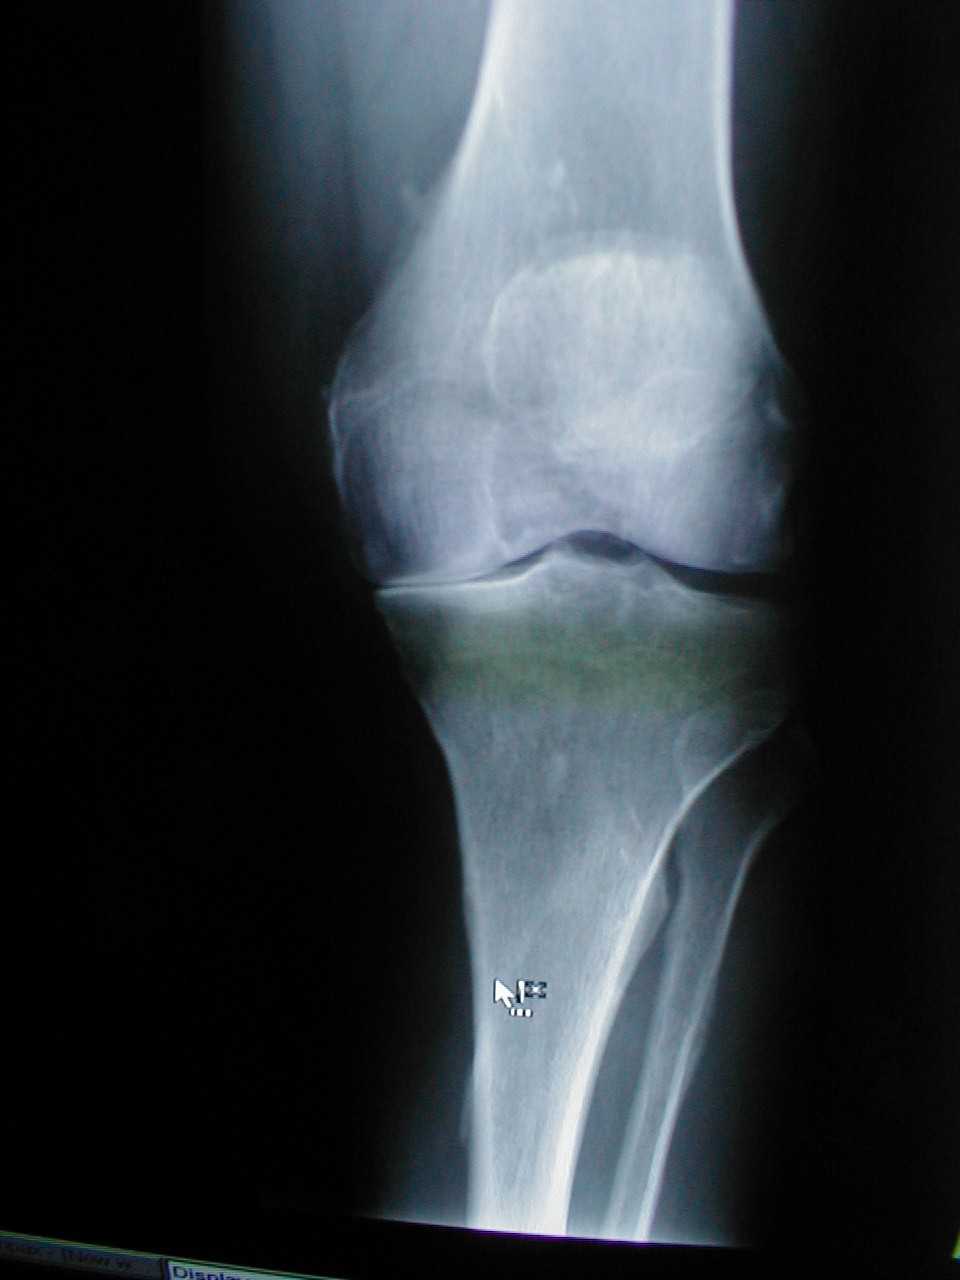

슬관절 주위의 점액낭이 급성 외상이나 만성적인 외상, 급성 감염, 만성 감염 등에 의하여 염증반응을 일으킨 것이다.

관절 상처, 감염, 관절염, 통풍 등이 있다. 직접적 외상에 의해 윤활낭에 염증이 생기는 경우에는 윤활액이 과잉 형성되고, 출혈이 일어나 붓게 된다. 오랫동안 앉아서 일하는 사람의 경우에는 고관절(엉덩이 관절) 주위에 있는 점액낭 중 좌둔부 윤활낭에도 이 질병이 생길 수 있다. 너비가 좁거나 높은 구두를 신는 사람은 발 부위나 아킬레스힘줄 주위에 이 질병이 생길 수 있다. 감염에 의한 경우 중 급성은 화농성 균에 의한 것이고, 만성은 결핵·진균·매독 등에 의한 것이다. 또한 대사성으로 혈중 요산이 증가하여 생기는 통풍성 윤활낭염은 슬관절 윤활낭에 잘 나타나며, 발이나 발목 등의 윤활낭에도 생길 수 있다.